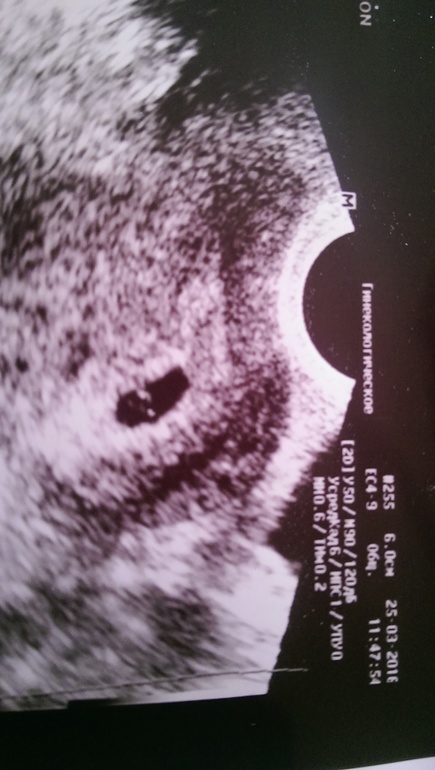

Нас увидели :) 5 недель

Сказать что счастлива - ничего не сказать :) нас увидели на узи :) правда мы-еще совсем крошки чтобы услышать СБ :)

Самая большая белая точечка с хвостиком :)

Там у вас смотрю все хорошо и уже эмбриончик немного видно

Да, хвостик :) врач хорошая, увидела распечатала:) Сердечко сказала попозже послушаем